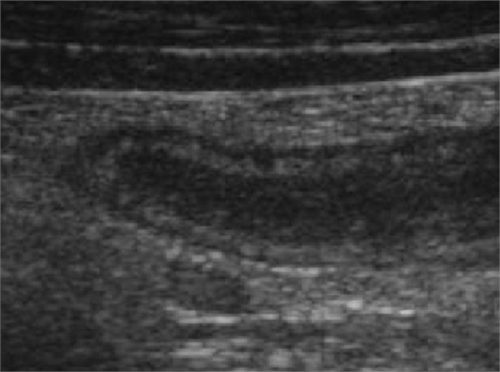

Hình ảnh ruột thừa viêm đơn thuần

Ruột thừa viêm trên mặt cắt trục dọc

Ruột thừa có hình dạng là cấu trúc ống với một đầu tịt trên mặt cắt trục dọc mà một số tác giả gọi là “dấu hiệu ngón tay”

Ruột thừa viêm trên mặt cắt trục ngang

Trên mặt cắt ngang ruột thừa có hình bia đạn với các vòng tròn đồng tâm (Đường kính lớn hơn 6mm, thành ruột thừa lớn hơn 3mm, ranh giới giữa các lớp có phần nhạt nhòa do tình trạng viêm phù nề, đè ép không xẹp).